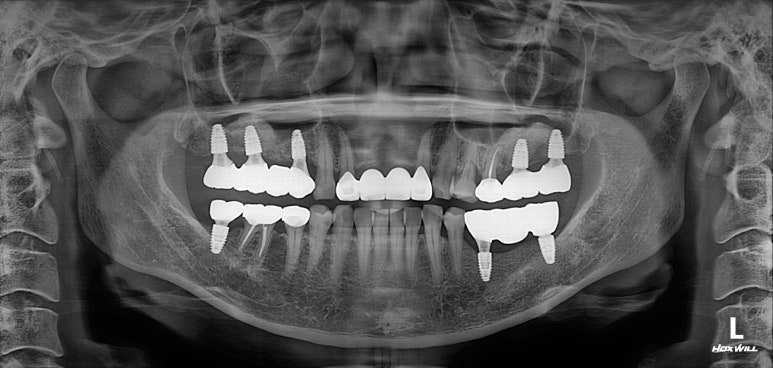

드디어 치료가 마무리 되는 날!..

마지막에 심었던 오른쪽 위 어금니 임플란트 골유착이 완성되었고, 그동안 나머지 부위들은 임플란트 크라운 치료를 완료 해두었습니다.

상당히 깔끔하게 제작되었고, 기존에 해둔 상악동 뼈이식술도 아주 잘 자리잡아주었네요.

3개월의 치유기간이 늘어 힘들 수도 있었지만, 치료를 잘 따라와주신 환자분께 감사의 말씀 전합니다.

그렇게해서 최종완료 후 치과용 파노라마 사진입니다!

치과치료에 대해 잘 모르시는 분이라 할지라도 보고 있으면, 치료가 조화롭게 잘 끝났구나.. 라고 아실 수 있으리라 생각합니다.

제가 제일 좋아하는 치과용 파노라마 비교 사진입니다.

앞으로 나란히를 한 것 같이 평행한 임플란트의 완성도는 항상 카타르시스를 느끼게 합니다.

정말 어디하나 나무랄 것 없이 치료가 잘 마무리되었는데, 물론 정말 열심히 정성들여 수술하는 저도 칭찬받아야 마땅하지만 늘 묵묵히 열심히 크라운 치료를 잘 해주는 우리 보철과 전문의 원장님들께 그 공을 돌리고 싶습니다.